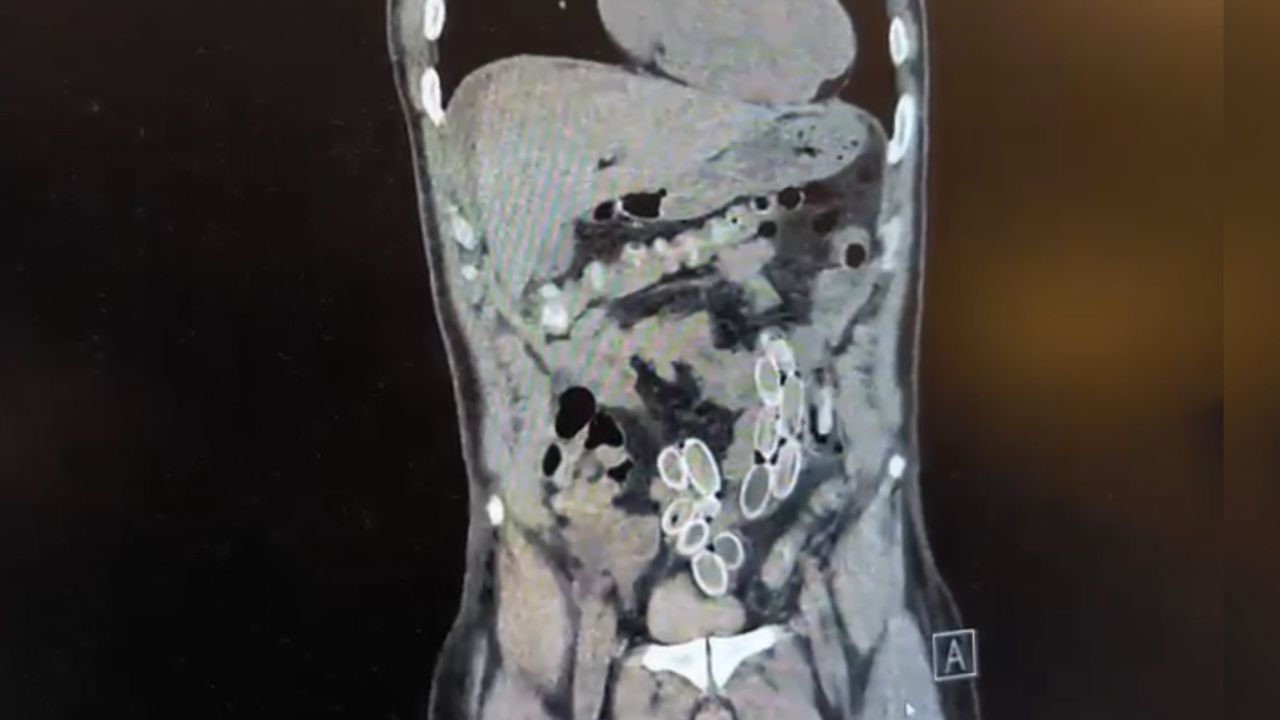

Fas’tan yaklaşık 3 bin kilometre uzaklıktan uçakla Türkiye’ye gelen Cüneyt G., 2 gün sonra karın ağrısı şikayetiyle Fulya’daki özel bir hastaneye başvurdu. Yapılan muayenenin ardından Cüneyt G.’nin tomografisi çekildi. Şüphelinin mide ve bağırsaklarında yabancı madde tespit edilmesi üzerine hastane yetkilileri durumu polis ekiplerine bildirdi.

İhbar üzerine çalışma başlatan Beşiktaş Asayiş Büro Amirliği ekipleri, doktorlarla görüşme gerçekleştirdi. Doktorların değerlendirmesi sonrası ameliyata alınan Cüneyt Ç.’nin bağırsaklarından, toplam ağırlığı 259,7 gram olduğu öğrenilen 49 esrar macunu çıkarıldı. Şüpheliye ait 1 adet cep telefonu da hastane yetkilileri tarafından polis ekiplerine teslim edildi.